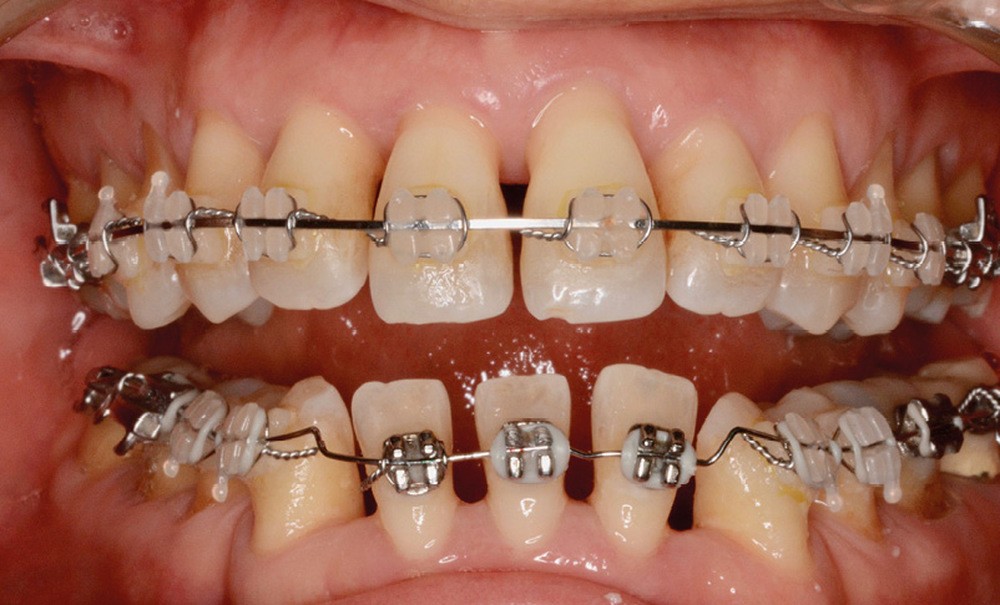

Traitement (fig. 10 à 20)

Un traitement en technique vestibulaire par appareillage multi-attaches .022 x .028 inch (prescription selon Roth) est entrepris, avec avulsion de prémolaires (15, 25, 34, 44).

La patiente ne supportant aucune cale occlusale, le collage de l’arcade mandibulaire est séquentiel afin de ne placer aucune attache en interférence occlusale. Le recul canin mandibulaire se fait grâce à des arcs sectionnels à boucle en Titane-Molybdène (TMA) .017 x .025 (fig. 10).

L’alignement et le nivellement maxillaires sont conduits en arc droit, et la mésialisation molaire réalisée en glissement, soutenue par des élastiques inter-arcades de classe III.

Le nivellement mandibulaire par ingresssion des incisives est mené via des arcs acier à la déformation avant de pouvoir recoller les brackets incisifs dans une position permettant de terminer le traitement en arc droit (fig. 11).